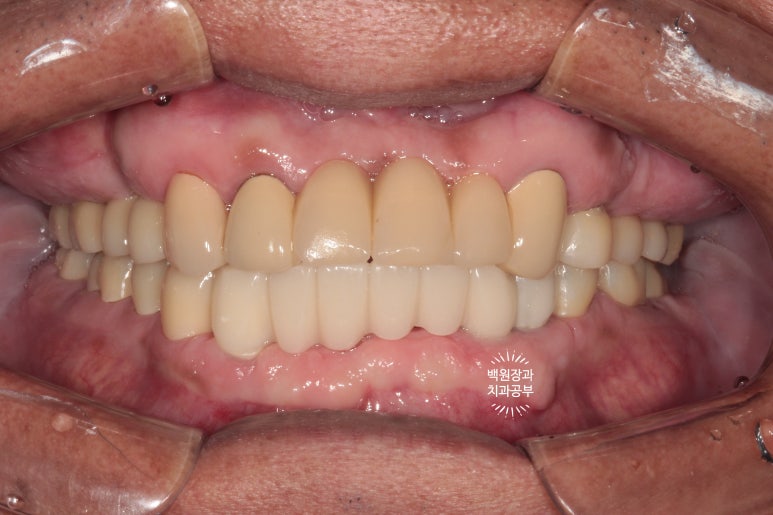

대망의 치료 완료!!!!!

Previous image Next image

우리 모두가 학수고대한 시간입니다.

보철물이 모두 완성되었어요.!!!

처음 이를 뽑기 시작한 때부터 정확히 9개월이 지난 시점입니다.

비용의 절감을 위해 기능적으로 문제가 없었던 위 앞니 보철물은 그대로 사용하고 계신 상태라

그 부분이 조금 부족한 느낌은 있지만,

새로 만든 치아들은 아주 조화로운 모양과 색상을 보여주고 있네요!!

위 아래 교합면 사진입니다.

임플란트를 교합면에서 보았을 때, 잘 식립되어 있는 경우 저렇게 동그라미들을 보실 수 있습니다.

바로 screw hole 인데요, 추후 임플란트를 수리해야 할 일이 있을 때, 다시 개방하는 screw 입구입니다.

현재는 레진으로 메꿔져 있어요.

아래 어금니 지르코니아 크라운들도 해부학적 형태가 잘 재현되어 있고,

조화로운 모양과 색상으로 거의 자연치와 흡사한 형태를 보여주고 있어요.!!!

들쭉날쭉한 치아 없이 조화로운 교합이 형성되어 있는 것을 보실 수 있을거에요.

교합평면도 가지런하게 형성되어 보입니다.